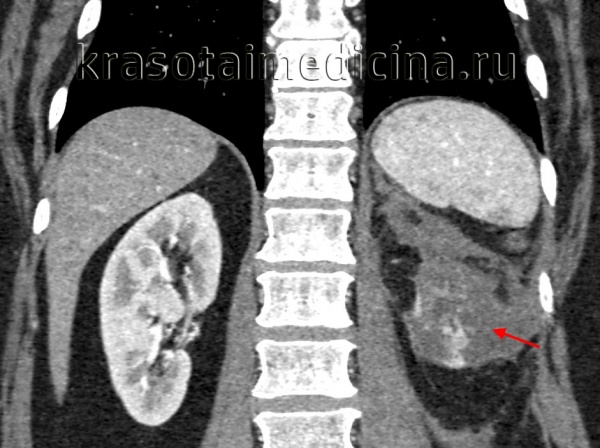

КТ ОБП/ЗП. Гнойное расплавление левой почки с формированием «мешка», заполненного гноем, с воспалительными изменениями прилежащей клетчатки.